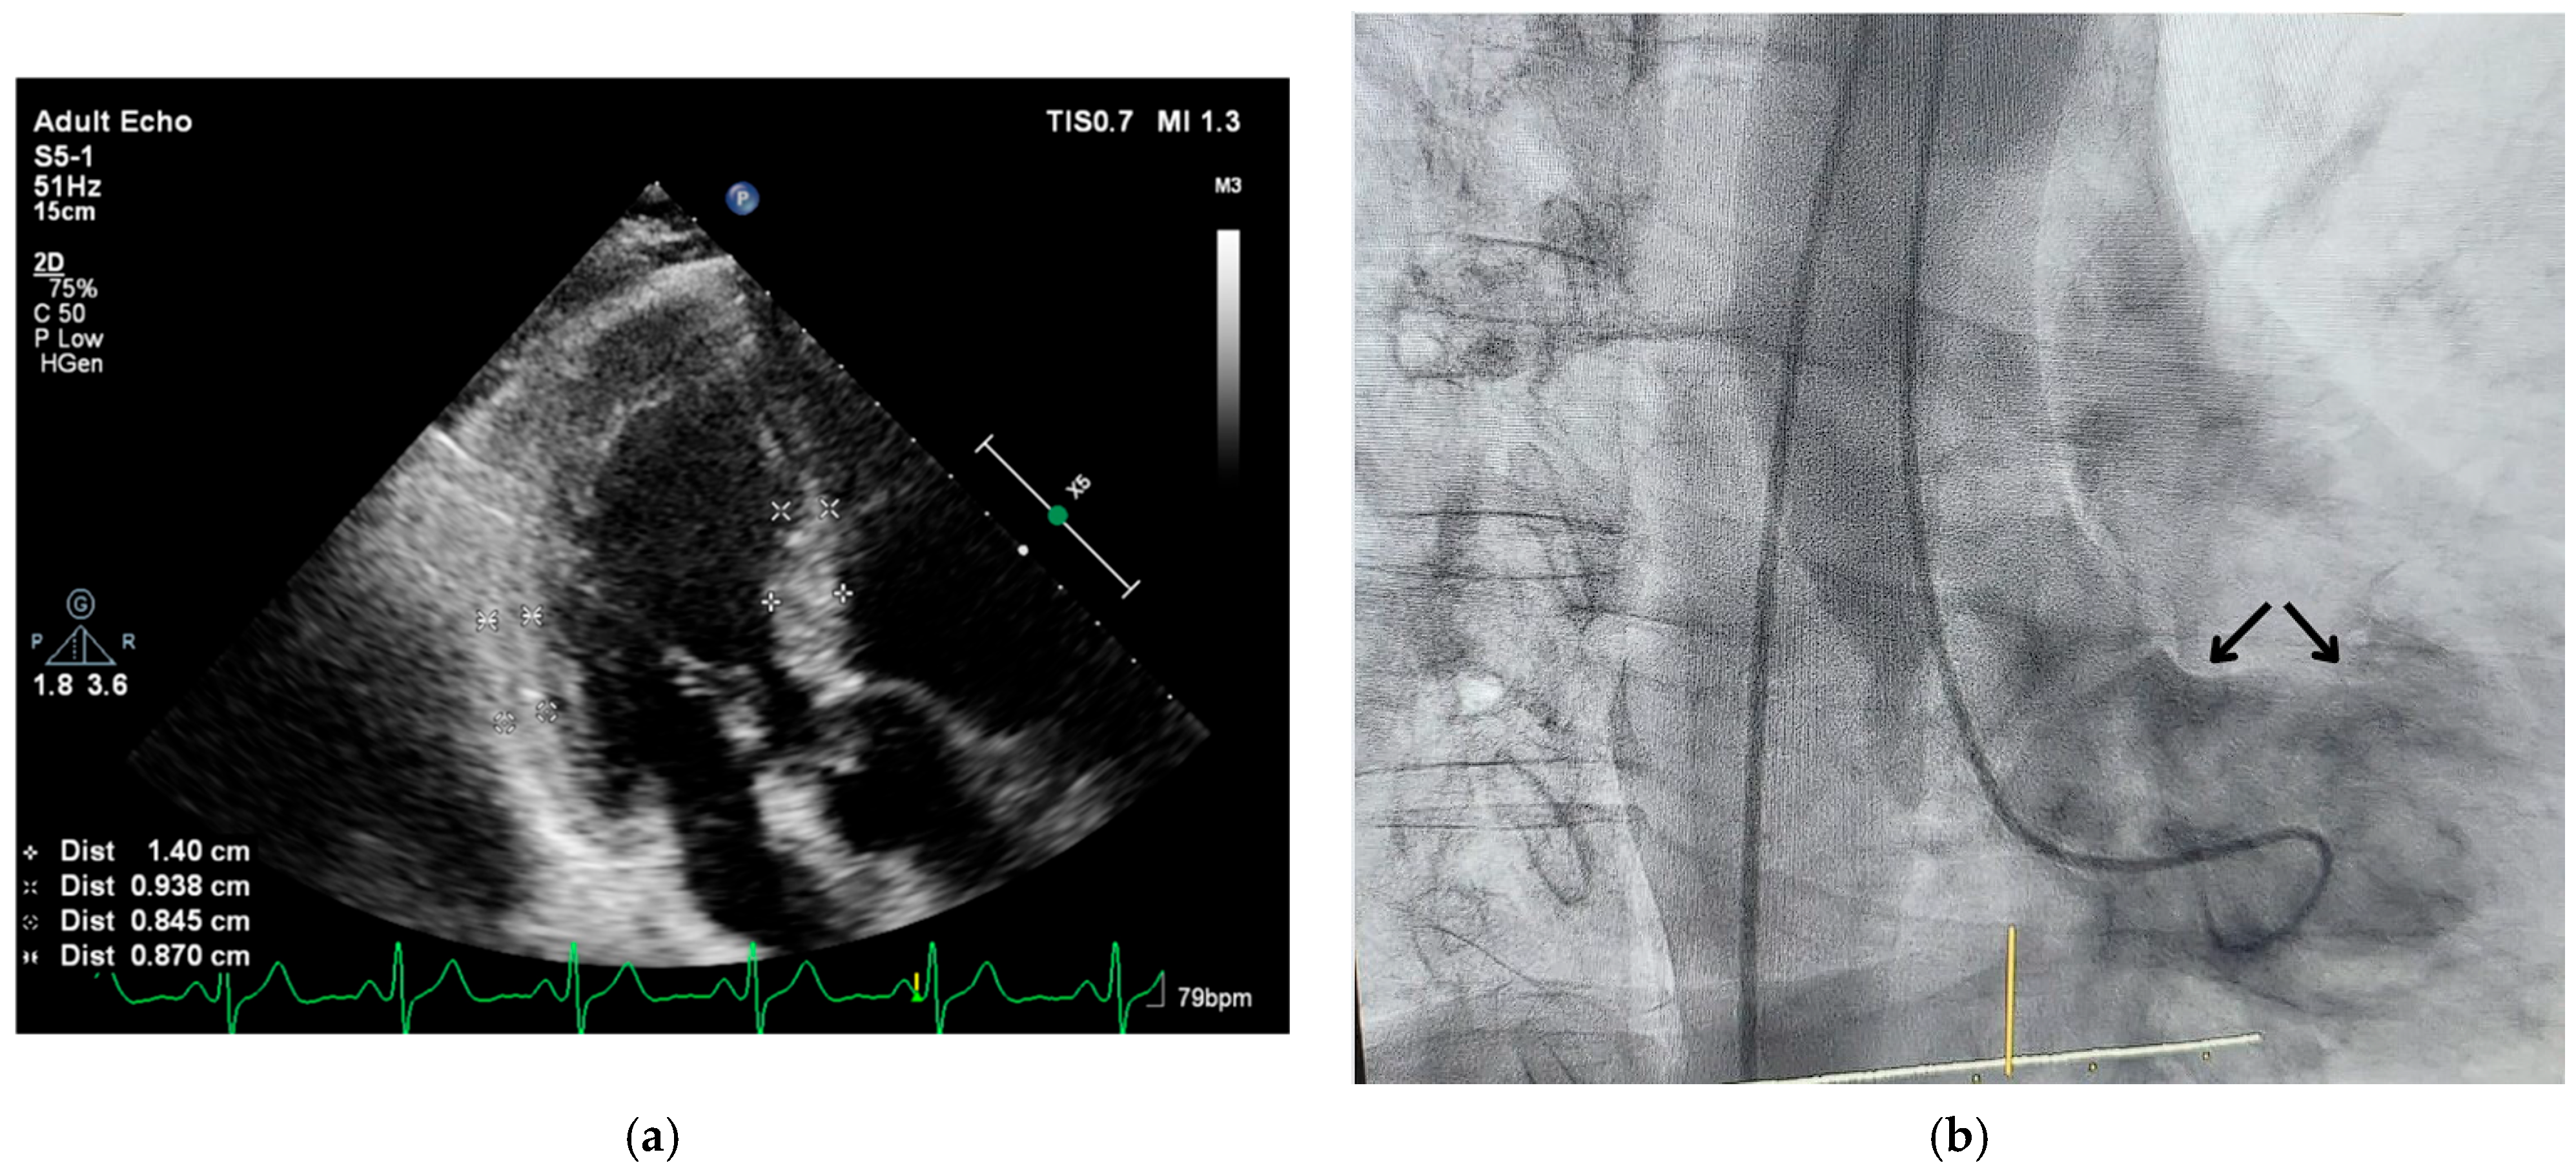

1.1. Real-Time Three-Dimensional Imaging

1.2. Stressed Heart Morphology

- Yalçin, F.; Shiota, T.; Odabashian, J.; Agler, D.; Greenberg, N.L.; Garcia, M.J.; Lever, H.M.; Thomas, J.D. Comparison by Real-Time Three-Dimensional Echocardiography of Left Ventricular Geometry in Hypertrophic Cardiomyopathy versus Secondary Left Ventricular Hypertrophy. Am. J. Cardiol. 2000, 85, 1035–1038. [Google Scholar] [CrossRef] [PubMed]

- Yalçin, F.; Yiǧit, F.; Erol, T.; Baltali, M.; Korkmaz, M.E.; Müderrisoǧu, H. Effect of Dobutamine Stress on Basal Septal Tissue Dynamics in Hypertensive Patients with Basal Septal Hypertrophy. J. Hum. Hypertens. 2006, 20, 628–630. [Google Scholar] [CrossRef]

- Yalçin, F.; Topaloglu, C.; Kuçukler, N.; Ofgeli, M.; Abraham, T.P. Could Early Septal Involvement in the Remodeling Process Be Related to the Advance Hypertensive Heart Disease? IJC Heart Vasc. 2015, 7, 141–145. [Google Scholar] [CrossRef] [PubMed][Green Version]